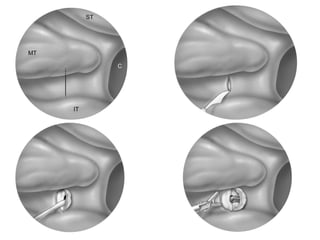

4) coagulation par voie chirurgicale endoscopique des artères

sphénopalatines.

LIGAURES DES ARTERES ETHMOIDALES

LIGATURE ENDOSCOPIQUE

ARTERE SPHENO PALATINE